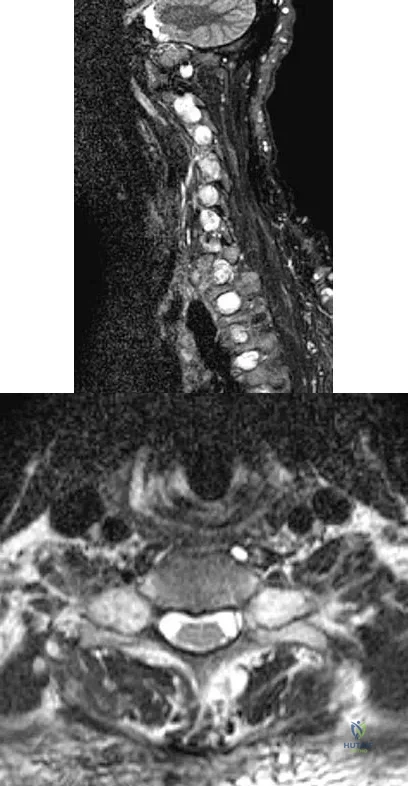

Figures 3a and 3b show the MRI scans of a patient with neck pain. What is the most likely diagnosis?

Explanation

Figures 23a and 23b show the MRI scans of a 50-year-old woman who has increasing gait disturbance. She reports three falls in the past week. Examination reveals hyperreflexia, motor weakness in the biceps and triceps, and a positive Hoffman's sign. What is the most appropriate treatment plan?

Explanation